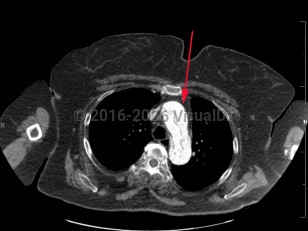

- CT angiogram of chest / abdomen / pelvis.

Aortic dissection is an intramural tear of the aorta. Aortic dissection is a life-threatening emergency. Tears often occur in the intimal layer of the aorta, with blood collecting in the medial layer. Back pain is the common presenting symptom, but it may also present with chest pain, dyspnea, or a new neurologic deficit. Syncope and hypotension occur less frequently. Aortic dissections most often occur in older men.

- Type A – dissection involving ascending aorta

- Type B – dissection that does not involve ascending aorta (ie, aortic arch and descending aorta)

- DeBakey I – ascending and descending

- DeBakey II – ascending only

- DeBakey III – descending only